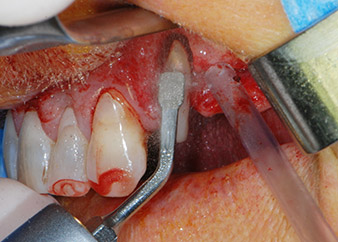

Un mese più tardi, nel giorno programmato per l'intervento, il dolore e l'infiammazione in corrispondenza del dente 24 erano minimi, ma era ancora presente mobilità di classe 2 secondo Miller. Dopo l'apertura dei lembi e la pulizia del tessuto periapicale e periradicolare infetto, l'estensione della mancanza ossea si è resa evidente (Figg. 2 e 3).

Tutto il tessuto osseo vestibolare e distale era mancante in corrispondenza della radice buccale. La possibilità di attacco era essenzialmente ristretta alla radice palatale, evidenziando la prognosi negativa preliminare. Anche il dente 27 mostrava un punto di attacco orizzontale ridotto e una rarefazione apicale minima (cfr. Fig. 1), senza sintomi clinici.

perdita totale di tessuto osseo e attacco

Fig. 2 e 3: Dopo aver sollevato i lembi, un mese dopo il pretrattamento endodontico e l'inizio della terapia periodontale sull'intera dentatura, la radice buccale del dente 24 mostrava una perdita totale di tessuto osseo e di punti di attacco.

Si è mantenuta , tuttavia, l'idea iniziale di conservare entrambi i denti come appoggi temporanei del ponte durante il periodo di sei mesi per l'osteointegrazione degli impianti. In seguito la situazione si sarebbe assestata. In primo luogo, in un tentativo di risolvere il problema entro-periodontale, la superficie radicolare rimanente è stata attentamente sbrigliata con apparecchiatura piezoelettrica (Piezomed di W&H con l'attacco S1 a spatola, progettato in origine per l'erosione della parete laterale del seno mascellare) Fig. 4).